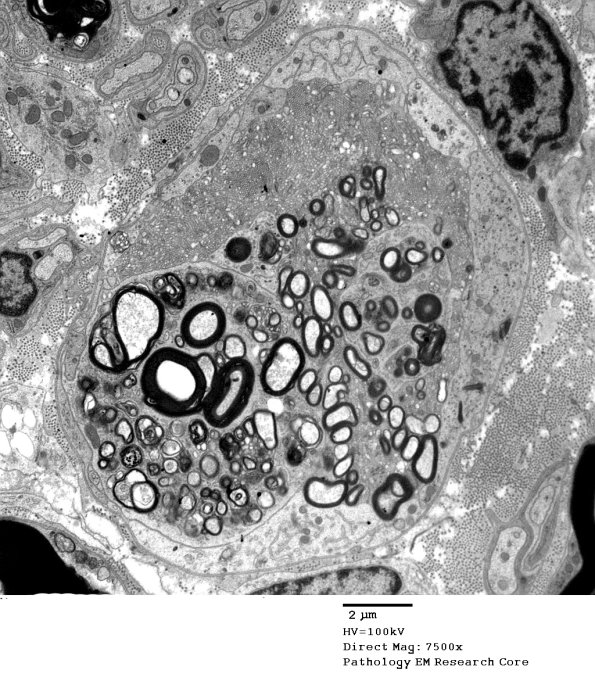

2G1-5 Multiple images of an impressively large degenerating axon with numerous elements. ---- 2G1 There are multiple patterns of injury in this axon.